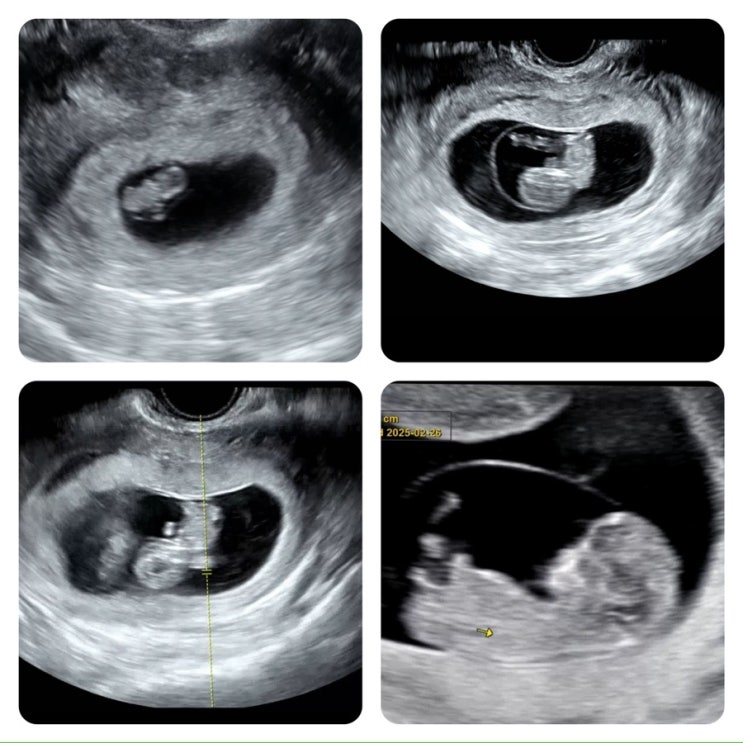

[임밍아웃] 5w~16w 기록+성별 공개_with 포글이♡

드디어... 합니다 ㅎㅎ 임밍아웃!!! (˶> <˶)♡ 내 블로그에 이런 소식을 전하는 날이 오다니..! 뭔...